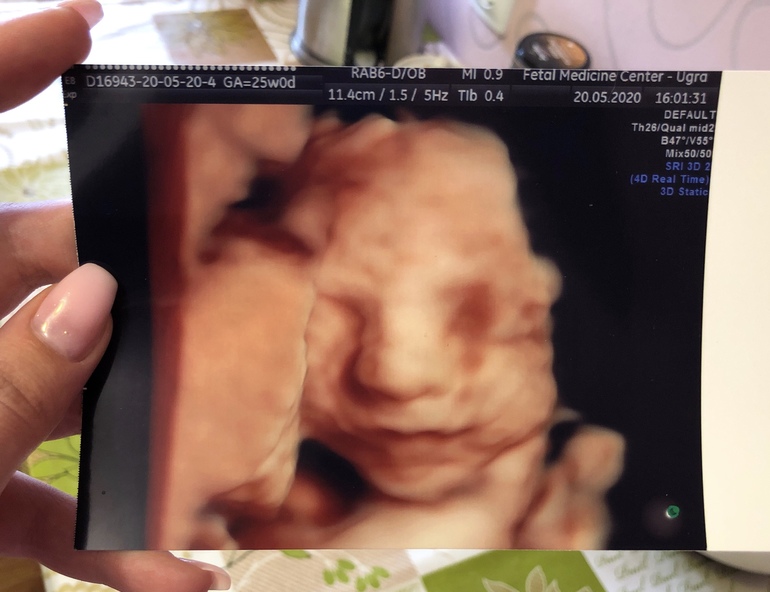

По состоянию нашей кнопки: на 18 неделе нам поставили диагноз КАПРЛ (левое легкое увеличено и сердце смещено вправо). После этого начались постоянные узи, консилиумы и настоятельные «рекомендации» врачей прервать беременность. После того, как все инстанции были посланы со своими «рекомендациями» на три веселые буквы, меня продолжили наблюдать но уже на отвали, обожаю нашу медицину (нет). На 25 неделе сходили на узи платно к лучшему узисту в городе. Малышка отлично развивается, все в полном порядке, но диагноз остаётся. Сказал не расстраиваться и что малышка обязательно родится, но возможно потребуется операция. На «рекомендации» нашего роддома покрутил у виска пальцем. А когда он показал нам ее в 3D мы чуть не расплакались 😍 пришли к выводу, что она моя копия 😅